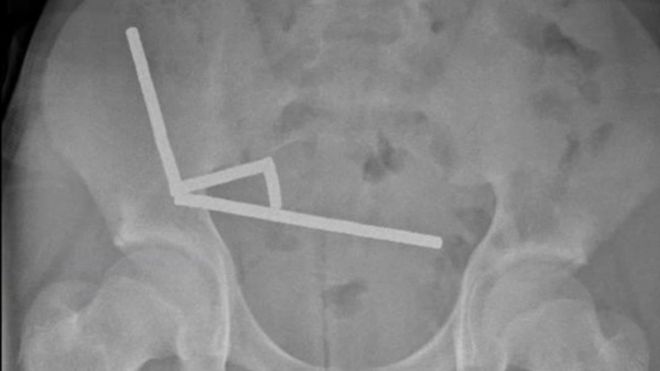

엑스레이 촬영 결과 의료진은 소년의 장 여러 부위에서 자석들이 사슬처럼 연결된 막대 4개를 확인했다. 복부 속에서 네오디뮴 자석들이 서로 강하게 달라붙어 막대 모양으로 뭉치면서 위험한 상황을 초래했다.

수술 과정에서 자석 사슬들은 소장과 맹장의 여러 구간에 흩어져 있는 것으로 확인됐다.

자석들이 서로 강하게 끌어당기면서 사이에 낀 조직의 혈액 공급이 차단됐고, 이로 인해 여러 부위에서 압박 괴사가 발생했다.

소년의 복부에서 막대 모양으로 뭉친 자석. 뉴질랜드 의학 저널 |